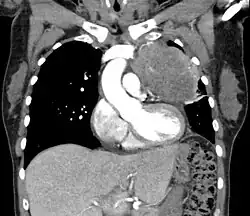

| Thymic carcinoma seen on CT. | |

Diagnosis of thymic carcinoma is based on a combination of clinical, radiologic, and biopsy findings. Most early cases are asymptomatic and found incidentally on chest radiographs as a mass in the anterior mediastinum. Further evaluation consists of additional imaging, such as CT, MRI, and PET, and tumor biopsy, which is the gold standard and provides the definitive diagnosis.[5] Biopsy may be done prior to surgery by fine needle aspiration or during the surgery with concomitant evaluation by the pathologist.[8] Other carcinomas with malignant spread to the thymus are on the differential diagnosis and must be excluded, as they may appear similar to thymic carcinoma on histopathological examination. [3]